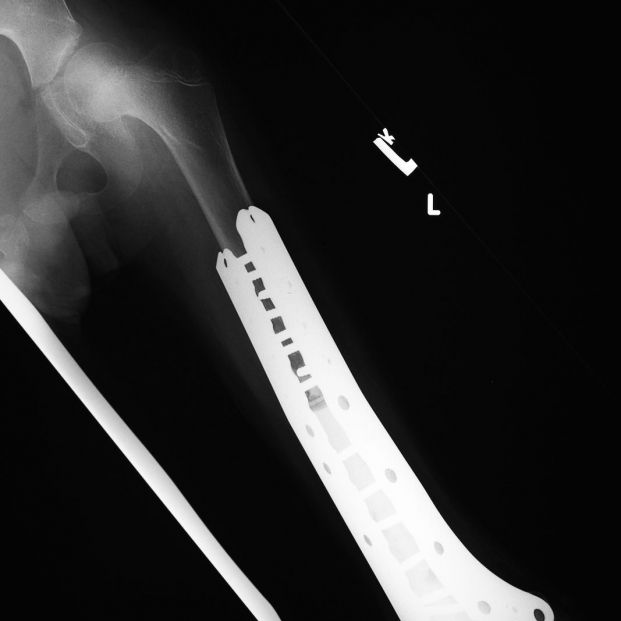

El osteosarcoma y los cánceres de hueso secundarios se diagnostican mediante una radiografía. También puede realizarse una resonancia magnética (RM) y tomografía computarizada (TC) para determinar la cantidad de hueso que ha sido destruida por el tumor y comprobar si éste se ha diseminado.

- Los rayos X, que muestran la ubicación, el tamaño y la forma de un tumor óseo. Si se detecta que hay un área anormal que puede ser cancerosa, es posible que el médico recomiende pruebas especiales de imagen. Aún cuando los rayos X sugieran que un área anormal es benigna, es posible que el médico quiera realizar pruebas adicionales, especialmente si el paciente está padeciendo dolores persistentes o inusuales.

Dentro de los rayos X, se pueden destacar las siguientes técnicas diagnósticas: